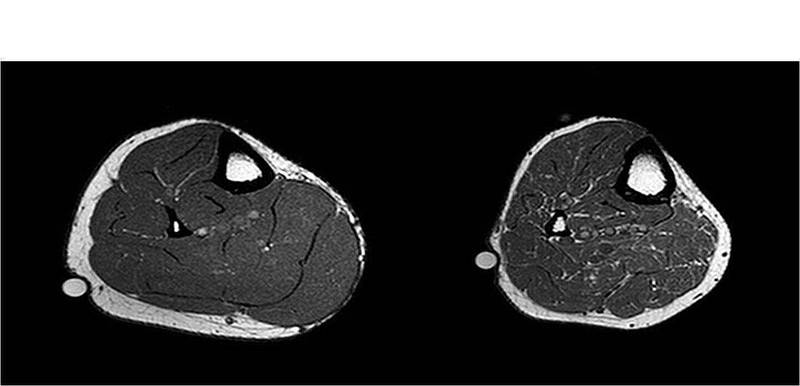

“We will monitor changes in muscle mass, volume and fat content in the participants using MRI; insulin sensitivity and inflammation in blood samples; and changes in protein synthesis and molecular signalling in muscle biopsies. These changes will indicate to us the impact of fish oil on the body in helping prevent against sarcopenia.